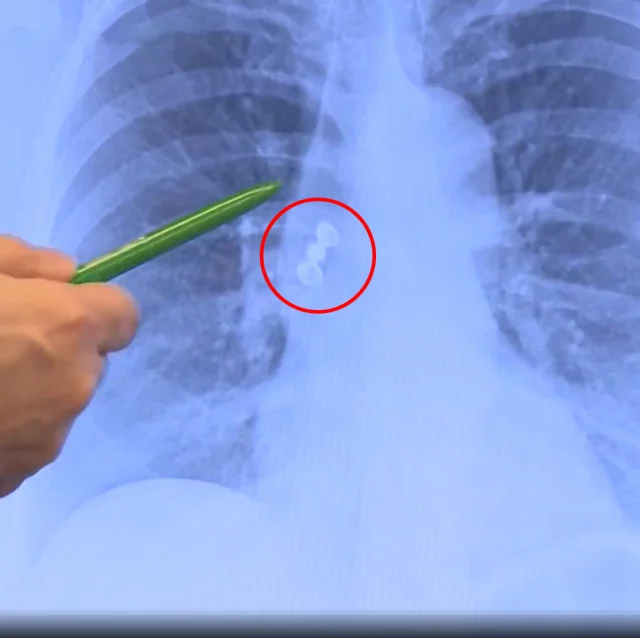

Xəstəxanada çəkilən döş qəfəsinin rentgeni hadisənin gedişatını dəyişib.

Müəyyən edilib ki, üç dişdən ibarət qapaq körpüsü qadının mədəsinə deyil, ağciyərinə düşüb.

Nadir hallarda rast gəlinən bu problem bronkoskopiya üsulu ilə aparılan əməliyyat nəticəsində həll olunub. Diş körpüsü qadının ağciyərindən uğurla çıxarılıb.